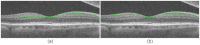

Segmentation of anatomical and pathological structures in ophthalmic images is crucial for the diagnosis and study of ocular diseases. However, manual segmentation is often a time-consuming and subjective process. This paper presents an automatic approach for segmenting retinal layers in Spectral Domain Optical Coherence Tomography images using graph theory and dynamic programming. Results show that this method accurately segments eight retinal layer boundaries in normal adult eyes more closely to an expert grader as compared to a second expert grader.